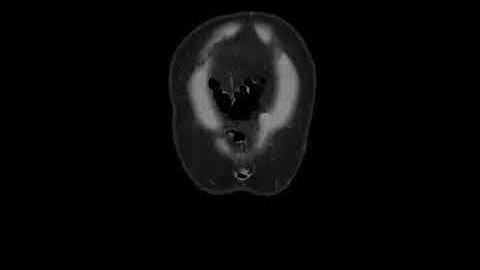

pseudomembranous colitis